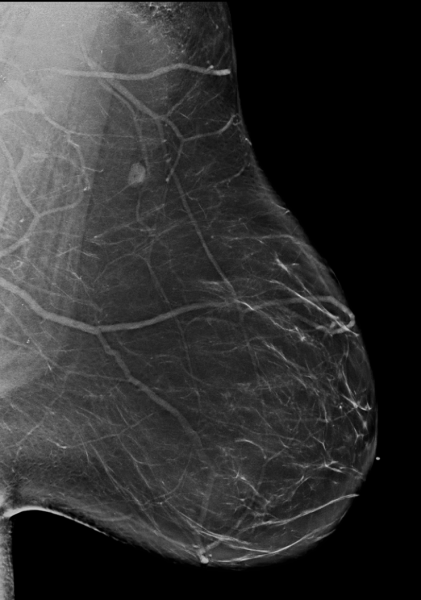

Breast density is divided into four categories, from lowest to highest amounts of fibroglandular tissue composition. Category A: Almost entirely fatty (least amount of fibroglandular tissue). Category B: Scattered fibroglandular tissue. Category C: Heterogeneously dense. Category D: Extremely dense (most amount of fibroglandular tissue).

Breast tissue is composed of a mixture of milk ducts, glands and supportive tissue, which is collectively called fibroglandular tissue and fat. The radiologist who reviews the mammogram analyzes overall breast density, which is the ratio of the amount of fibroglandular tissue to fatty tissue. Women with dense breasts have more fibroglandular tissue than fatty tissue. Fibroglandular tissue appears white on a mammogram and fat appears black. It becomes harder to detect a white cancer against a white background — imagine trying to find a polar bear in a blizzard. Dense tissue is harder to see through to detect abnormal findings. As breast density increases, cancer detection becomes more difficult. Additionally, breast cancer risk rises with increasing breast density. Multiple studies have indicated that there is a two- to six-fold increased risk of breast cancer for a woman who has an extremely dense breast versus a woman with an almost entirely fatty breast.4

Breast density is divided into four categories, from lowest to highest amounts of fibroglandular tissue composition:

Category A: Almost entirely fatty (least amount of fibroglandular tissue)

Category B: Scattered fibroglandular tissue

Category C: Heterogeneously dense

Category D: Extremely dense (most amount of fibroglandular tissue)